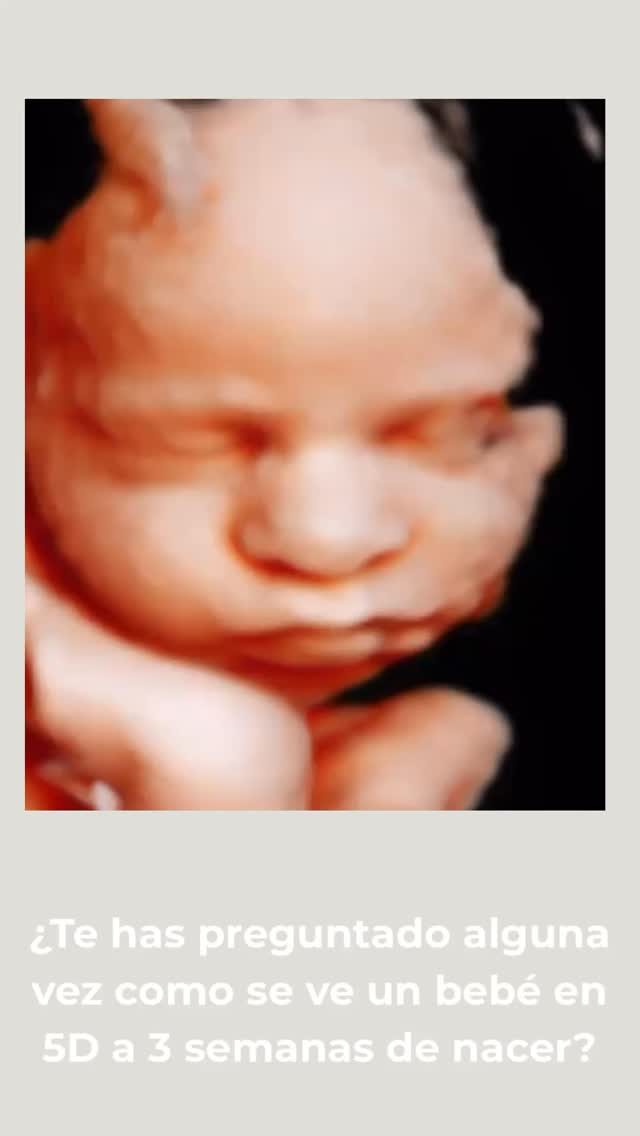

Ecografía 5D

Descubre a tu bebé antes de su nacimiento con nuestras ecografías 5D. Ver sus gestos, escuchar su latido y compartir ese momento con tu familia es una experiencia inolvidable.

Hiperrealismo